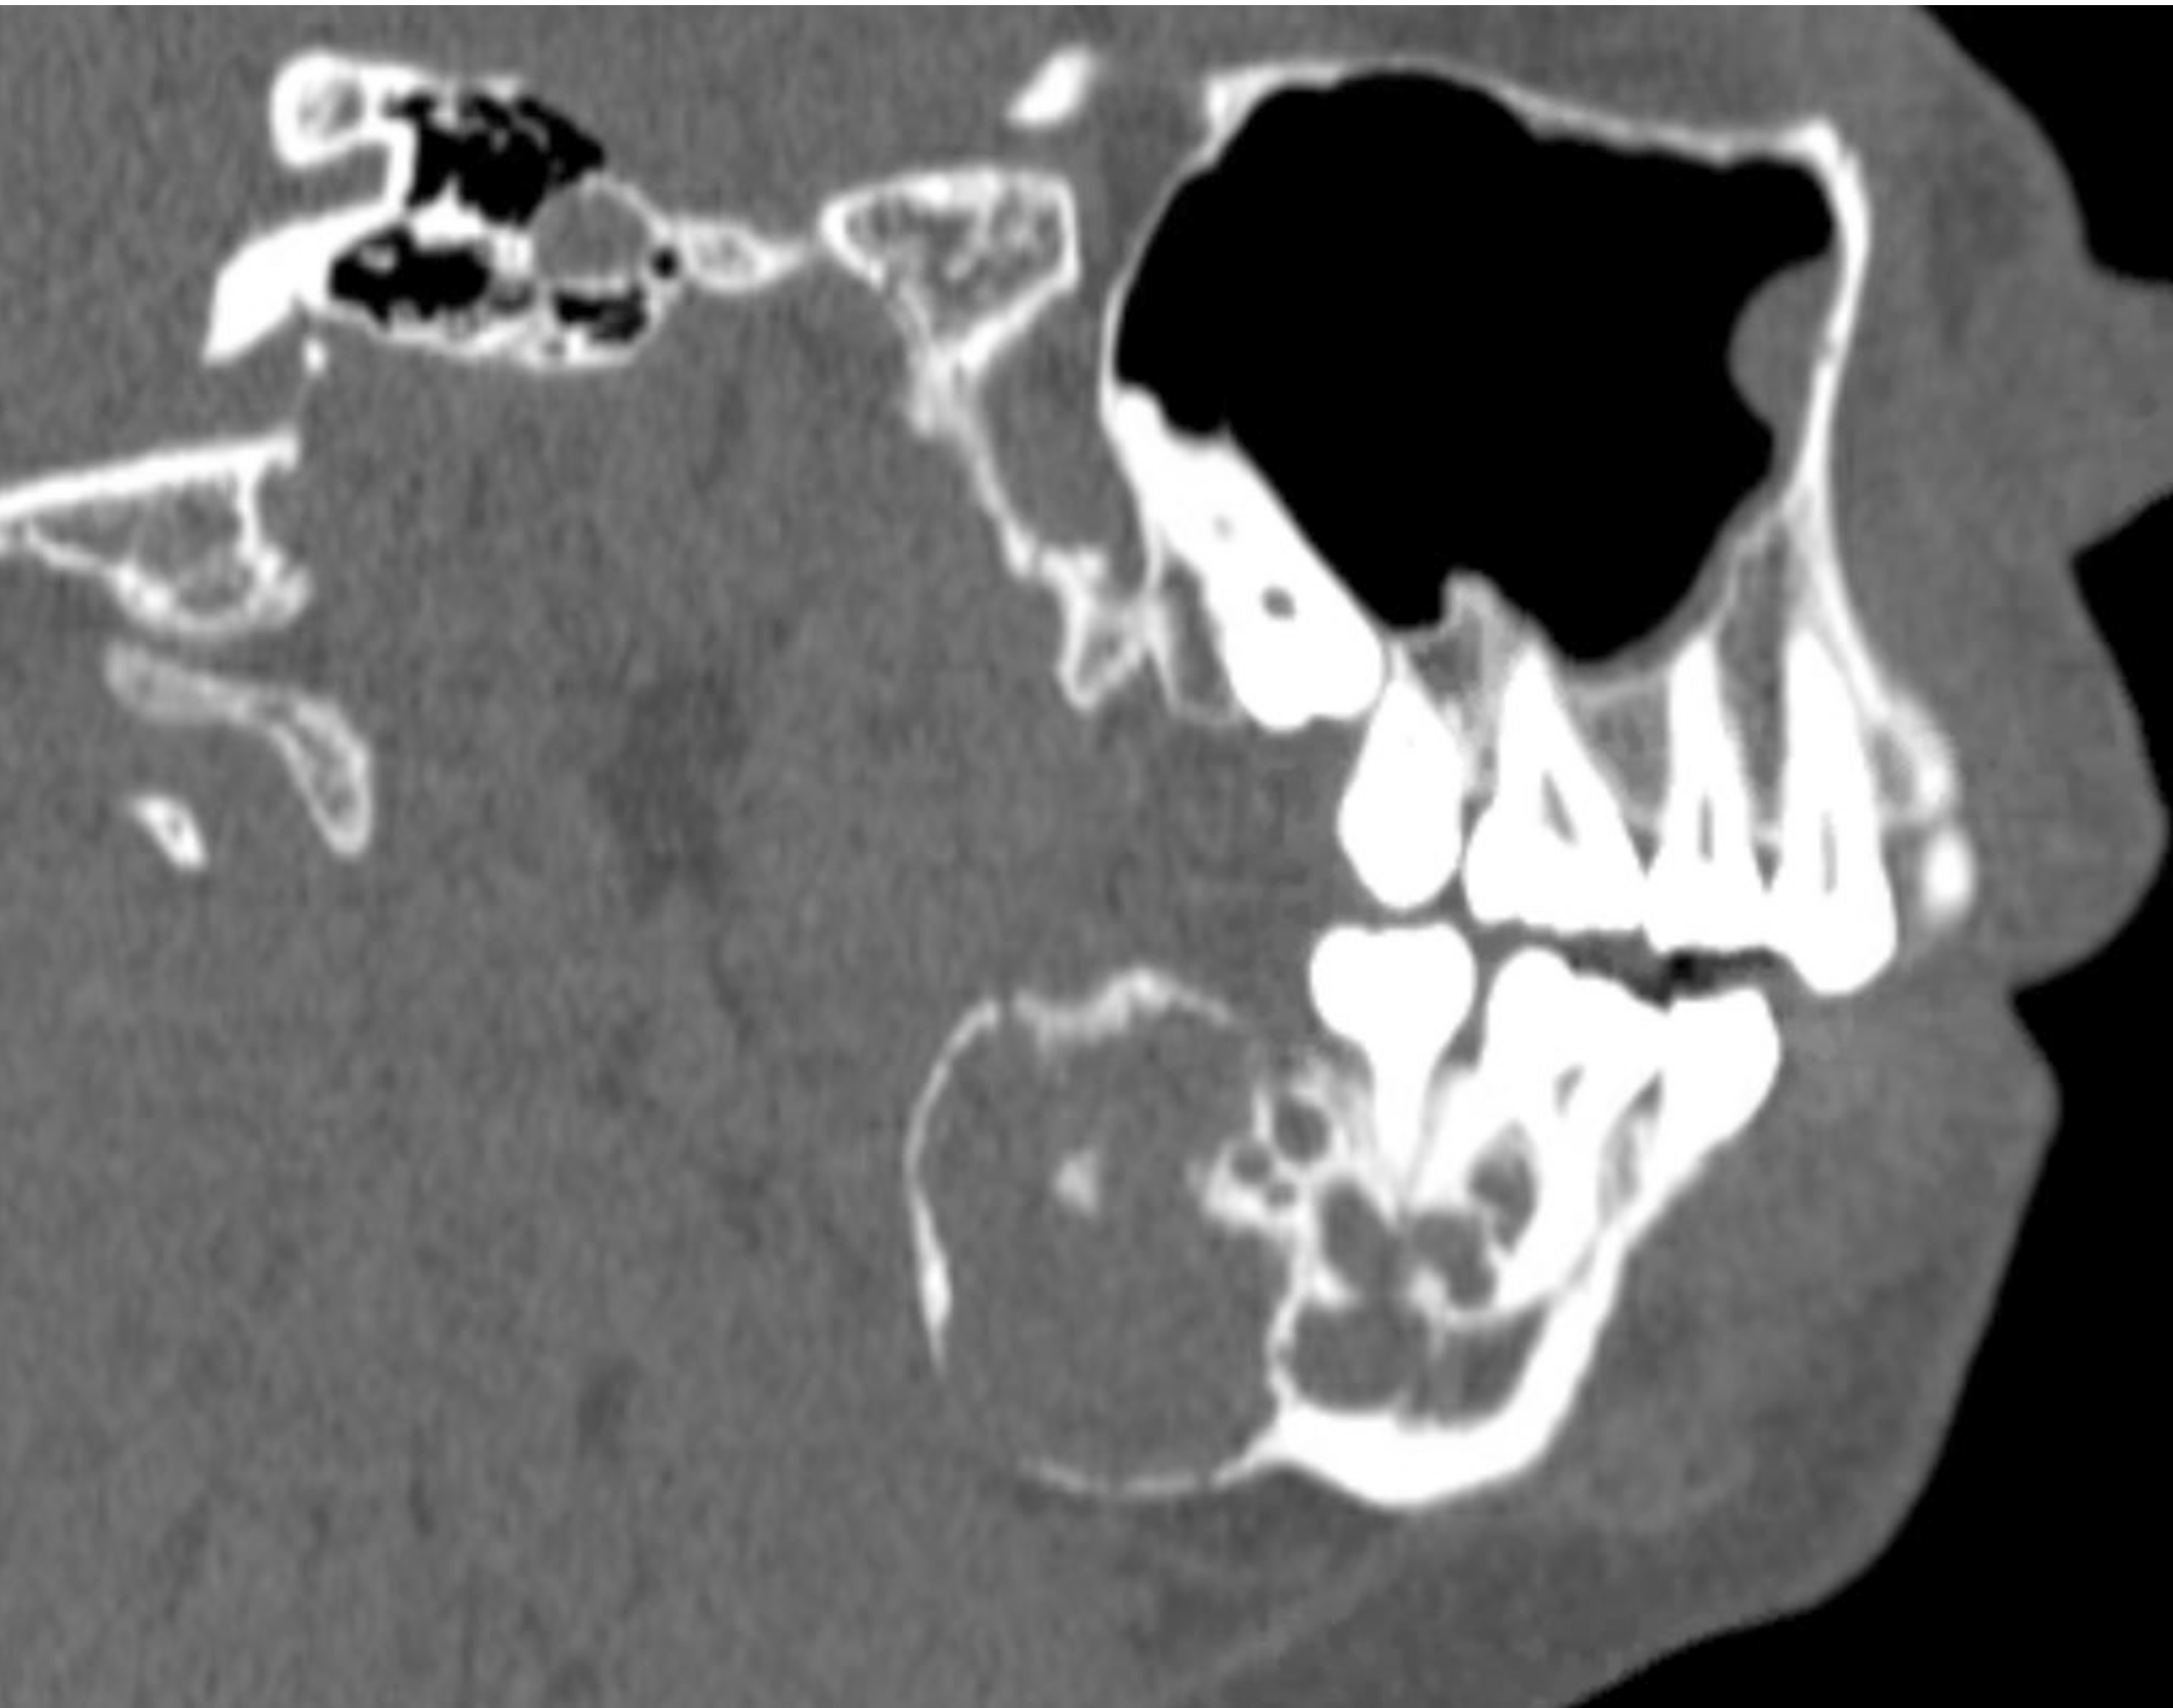

Radiology description

- Ameloblastoma, conventional

- Expansile multilocular radiolucency, well defined, corticated border

- Some cases exhibit classic soap bubble appearance

- May or may not be associated with impacted tooth / teeth

- Resorption or displacement of tooth roots

- Reactive bone formation may occur, most commonly in desmoplastic ameloblastoma, which may resemble a fibro-osseous lesion radiographically due to the presence of osteoplasia

- May have a unicystic radiographic appearance on plain images; requires microscopic examination for distinction from ameloblastoma, unicystic type (Dentomaxillofac Radiol 2018;47:20170288)

- Ameloblastoma, unicystic type

- Unilocular radiolucency, well defined, corticated border

- Often associated with an impacted tooth, specifically mandibular third molar

- Root resorption may occur

- Cortical perforation in 33% of cases

Radiology images